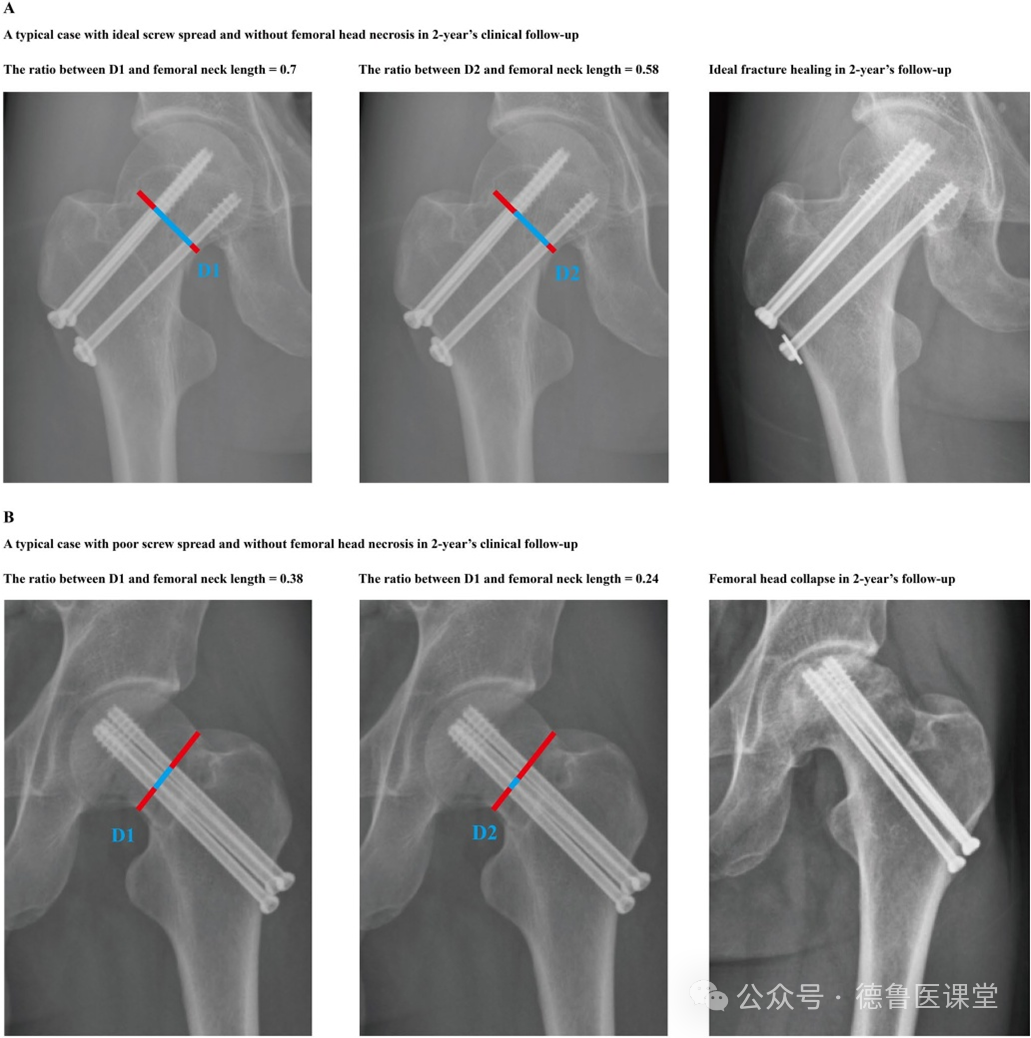

A maior distância entre os parafusos pode reduzir o risco de necrose do colo femoral a curto prazo, otimizando a estabilidade da fixação em pacientes com fratura do colo femoral submetidos à fixação com parafusos canulados em triângulo

2025/12/15Shengyu Wan, Jian Zhang, Tongzheng Zhang, Lijunpeng Jia, Xiaozhong Luo, Weixiang Shi, Jiaqi Wang, Jingchi Li, Xi Chen & Wenqiang Xu Contexto Uma complicação primária associada às fraturas do colo femoral é a necrose da cabeça femoral. i...